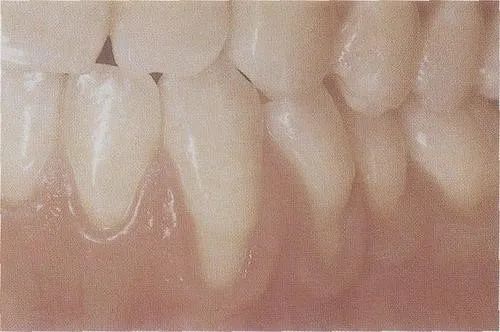

值得一提的是,很多时候,这种牙龈退缩是有可能被治疗的,通过改善不良口腔习惯,结合牙周治疗,配合移植自体组织或人工材料的软组织手术,抑或是合理的充填和修复治疗,牙龈和牙齿的外观能够得到一定程度的恢复。

过度刷牙导致的牙颈部磨耗和牙龈退缩

刷牙、咬合创伤引起牙龈退缩